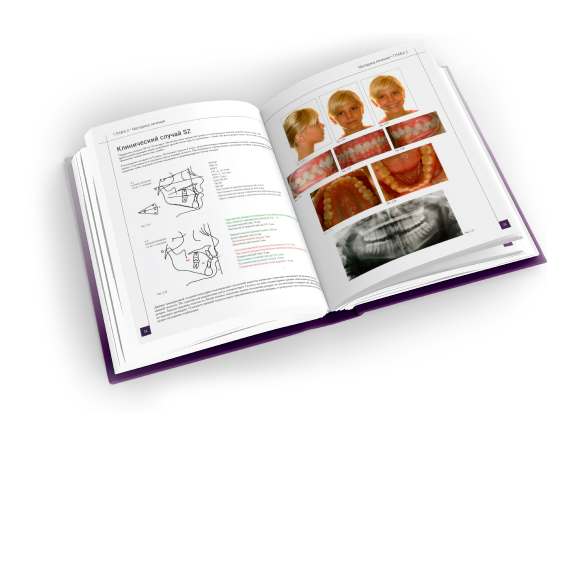

Арт:

760-0062

В наличии

Арт: